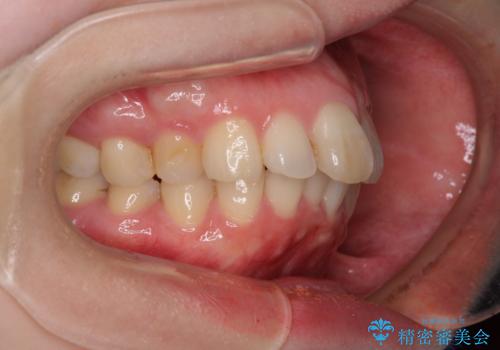

カリエール・ディスタライザーを用いたことで上顎前歯の突出感はスムーズに解消され、歯列不正は1年半ほどでほぼ改善することができました。

しかし、その後インビザライン特有の奥歯がうまく噛めないという問題が長引き、改善に1年近い期間を要することとなりました。